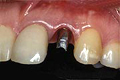

| ■施術前 | ■施術後 | |||

![]() |